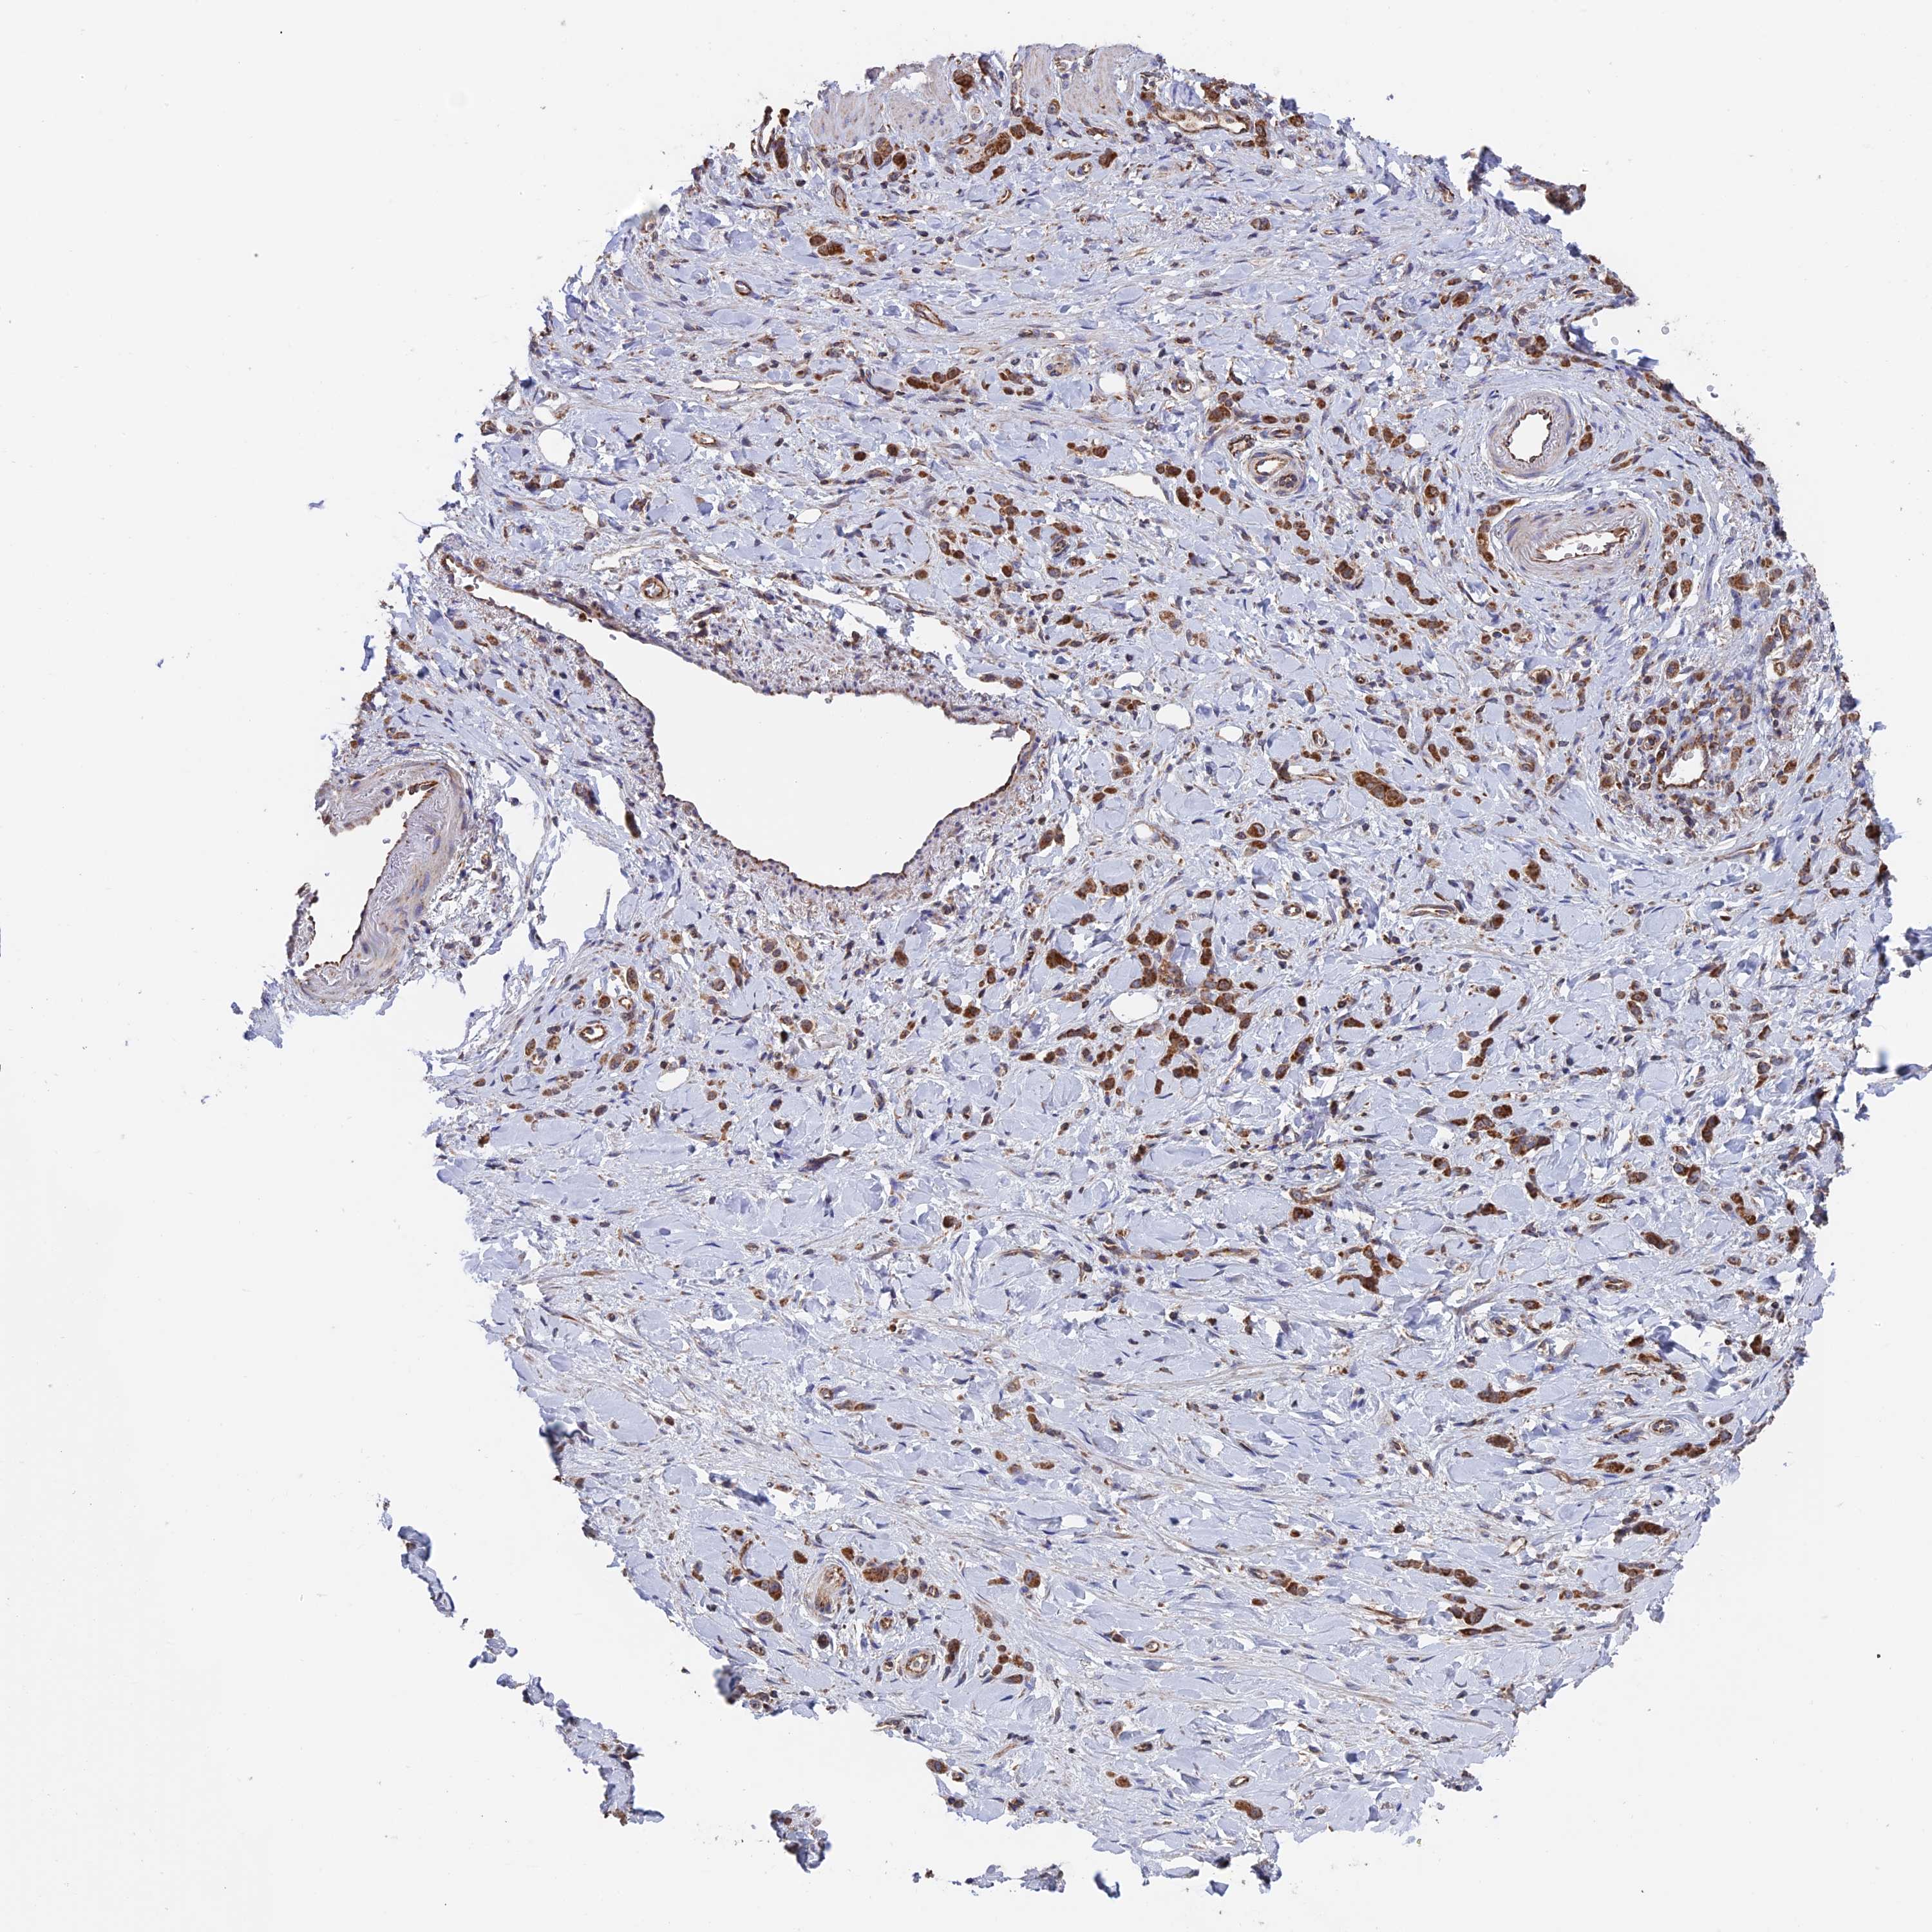

STOMACH CANCER - Protein expressioni

A mouse-over function shows sample information and annotation data. Click on an image to view it in a full screen mode. Samples can be filtered based on level of antibody staining by selecting one or several of the following categories: high, medium, low and not detected. The assay and annotation is described here.

Note that samples used for immunohistochemistry by the Human Protein Atlas do not correspond to samples in the TCGA dataset.

Antibody stainingi

Antibody staining in the annotated cell types in the current human tissue is reported as not detected, low, medium, or high, based on conventional immunohistochemistry profiling in selected tissues. This score is based on the combination of the staining intensity and fraction of stained cells.

Each image is clickable and will lead to virtual microscopy that enables deeper exploration of all samples and also displays staining intensity scores, fraction scores and subcellular localization as well as patient and tissue information for each sample.

Antibody HPA042593

Antibody HPA042719

Staining

High

Medium

Low

Not detected

Intensity

Strong

Moderate

Weak

Negative

Quantity

>75%

75%-25%

<25%

None

Location

Nuclear

Cytoplasmic/membranous

Cytoplasmic/membranous,nuclear

Adenocarcinoma, NOS